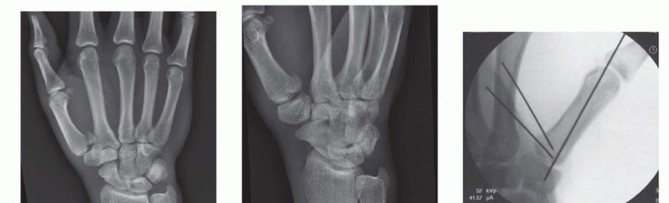

Closed Reduction and Percutaneous Pinning (CRPP)

CRPP is the treatment of choice for classic Bennett fractures where the volar-ulnar fragment is too small to reliably accept a lag screw, yet the joint can be anatomically reduced closed. The reduction maneuver is highly specific, designed to counteract the deforming forces of the APL and Adductor Pollicis. Longitudinal traction is applied to the thumb, followed by palmar abduction and pronation. Direct pressure is then applied to the dorsal-radial aspect of the metacarpal base, effectively pushing the shaft back into the anatomic cradle of the intact volar-ulnar fragment.

Once anatomic reduction is confirmed via multi-planar fluoroscopy, percutaneous fixation is achieved. Typically, two 0.045-inch or 0.062-inch Kirschner wires are utilized. The first wire is driven from the dorsal-radial aspect of the metacarpal shaft directly into the trapezium, effectively neutralizing the proximal pull of the APL. A second wire is often placed transversely from the first metacarpal shaft into the second metacarpal to control rotation and maintain the web space. Pins are cut outside the skin and capped to facilitate easy removal in the clinic.